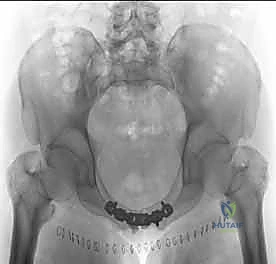

بمجرد استعادة الوضع الصحيح للعظام، يقوم الدكتور هطيف بتثبيتها باستخدام صفيحة معدنية متخصصة (غالباً صفيحة إعادة بناء متعددة الثقوب مصنوعة من التيتانيوم أو الفولاذ المقاوم للصدأ الطبي). يتم تثبيت هذه الصفيحة عبر المفصل العاني باستخدام مسامير قشرية (Cortical Screws) تُغرس بعمق في عظام العانة الصلبة لضمان تثبيت قوي يتحمل ضغط الجسم.

بعد التأكد من قوة التثبيت من خلال الأشعة السينية داخل غرفة العمليات (Fluoroscopy)، يتم إغلاق الجرح على طبقات باستخدام خيوط جراحية تجميلية قابلة للامتصاص، مع وضع أنبوب تصريف (درنقة) لمنع تجمع السوائل.